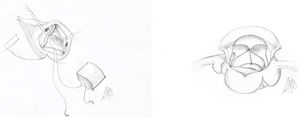

Presentamos una serie breve de 3 pacientes (tabla 1) de corta edad con afección de la válvula sigmoidea sistémica. Habida cuenta de su pequeño tamaño, la imposibilidad de realizar el procedimiento de Ross y la escasa experiencia en técnicas de reparación, optamos por una estrategia más simple previamente descrita por Hosseinpour et al.6. Básicamente, se trata de confeccionar un cilindro de pericardio a partir de un rectángulo (fig. 1), cuyos lados miden D y 4,5D (siendo D el diámetro de la raíz aórtica). Como alternativa al pericardio autógeno, al tratarse de reintervenciones, usamos uno equino libre de glutaraldehído (Matrix Patch™, Auto Tissue Berlin GmbH, Berlín, Alemania) y de textura similar al nativo. Finalmente, dicho cilindro es implantado7 en la raíz (fig. 2) mediante una sutura circular (anillo) y 3 verticales (comisuras).